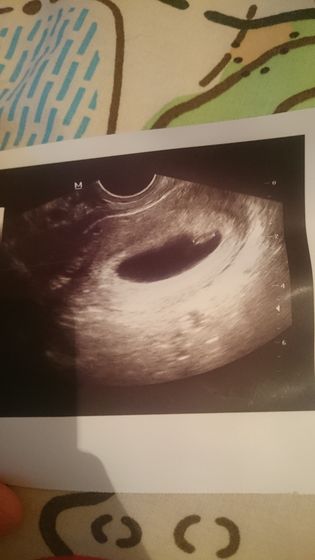

Ходила прикрепляться в поликлинику, но до нового года ни одной свободной записи. И чтобы удостовериться, что всё хорошо сегодня пошла на УЗИ. У нас всё хорошо по УЗИ 6 недель 5 дней (вообщем то как и по моим подсчетам), размер плодного яйца 41мм, КТР 6,9 мм; желточный мешок 4 мм. Так же посчастливилось услышать сердце ? 121 уд/мин. Решила, что буду вставать на учёт после новогодних праздников. Ничего не болит и тошноты на этой неделе небыло.

Как 41 мл???)) у всех кого читала на сроке 6-7 недель плодное яйцо около 18-20 мл ))

Там не мл, а миллеметры написаны, в заключение написано 41мм, врач сказала всё в норме ?

Вы видите на фото оно не круглое, а овальное. Поэтому и размер больше по длине